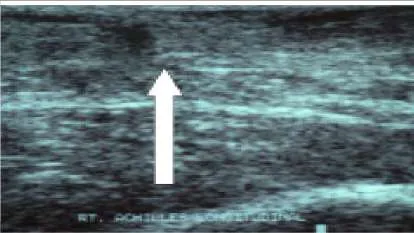

Question 22:

This slide (the arrow is pointing in the direction of the pathology) illustrates which of the following conditions of the Achilles tendon:

Correct Answer: Acute tendon rupture

Explanation:

This ultrasound is a longitudinal section of the Achilles tendon demonstrating acute rupture. Note the defect in continuity of the tendon below the skin surface. No tendon defects are noted in paratendinitis and tendinosis.